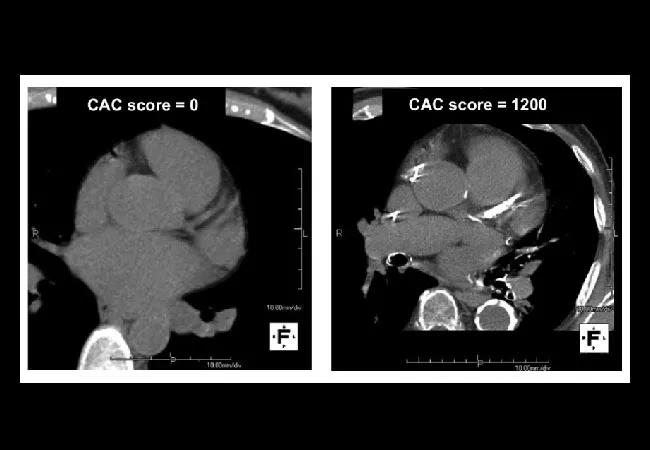

Coronary Artery Calcium Scoring: A Valuable Tool in Primary Care

In the September 2018 issue of Cleveland Clinic Journal of Medicine, Parikh and colleagues6 review coronary artery calcium scoring, a diagnostic test for coronary artery disease. They conclude that calcium scoring is strongly predictive but should be reserved for patients at intermediate risk, to help them decide about treatment [see this Consult QD post excerpting the portion of their review focusing on recommendations]. This is clearly the right approach, but the authors leave the term “intermediate” undefined, and their clinical examples offer too little guidance as to where the borders lie.

Because calcium scoring is a direct test for disease, it is extremely predictive. When added to risk-factor models, it substantially improves discrimination9 and exhibits excellent calibration.10 This is true whether the outcome is a major cardiovascular event or death from any cause.